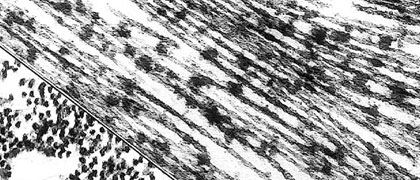

William I. Rosenblum, M.D., Professor Emeritus, Virginia Commonwealth University. The original image is part of an online "neuropathology minicourse" available at: www.pathology.vcu.edu/education/WirSelfInst/dementias.html.